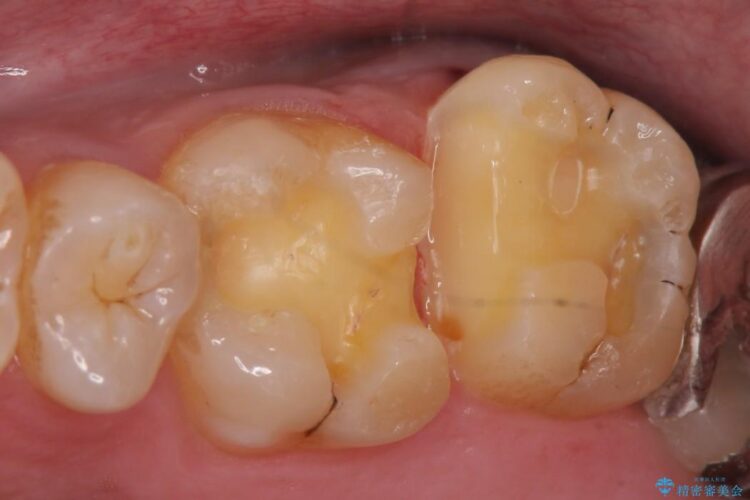

古い詰め物を外し、白く審美性の高いセラミックインレーにて再治療を行うこととしました。

銀歯と比べて本来の歯と自然になじむ仕上がりにとてもご満足いただけました。

今回は保険で治療してあった銀歯を審美性からセラミックインレーにて再度治療しました。

セラミックスは、見た目の審美性だけでなく劣化がしにくいことや金属アレルギーのリスクがないことがメリットとしてあげられます。